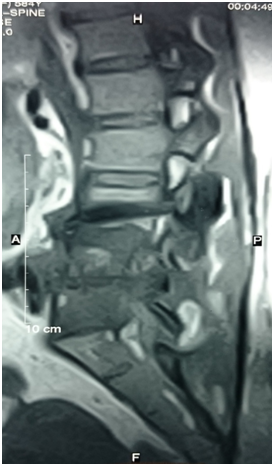

She was referred to a neurosurgeon, who decided to do an operation for this paraspinal mass that surprisingly was simply a bag of pus and fixation was done (Figure 3). After surgical drainage, cytopathological examination of the drained material was free of any malignant cells and culture of the drained pus confirmed the same organism and since then she was better.

Figure 3 Bone scan, focal area of intense radioactive tracer uptake is seen the right pedicle of 4th lumbar spine?? Metastatic lesion otherwise the remained of scanned skeleton is free.

This what exactly happened to our case with normalization of liver function tests by proper treatment of her sepsis. Imaging studies including plain x-ray and CT could be useful. However, MRI is the most sensitive, radioisotope is a helpful adjunct, and biopsy (either percutaneous needle or open surgical) is generally needed to confirm the clinical and/or radiographic suspicion. Samples should be sent for aerobic, anaerobic, mycobacterial and fungal culture and pathology.

In our case, MRI suggested metastatic bone lesion which was changed to a diagnosis of paraspinal abscess on surgery indicating the mandatory need for confirmation of the diagnosis through biopsy. Surgical drainage of the paraspinal abscess under coverage of systemic antibiotic was the treatment of choice in this case as reported in literature.13